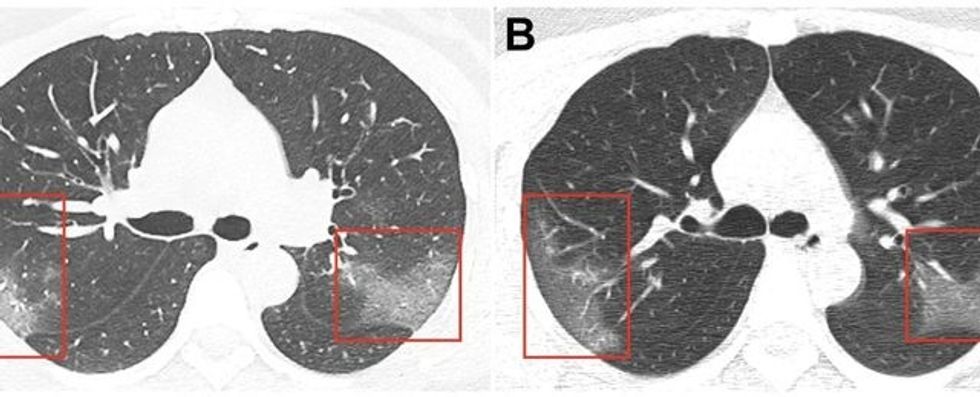

Wilson thotë se ka prova që pneumonia e shkaktuar nga Covid-19 mund të jetë veçanërisht e rëndë. Wilson thotë se rastet e pneumonisë koronavirus kanë tendencë të prekin të gjithë mushkëritë, në vend të vetëm pjesëve të vogla.